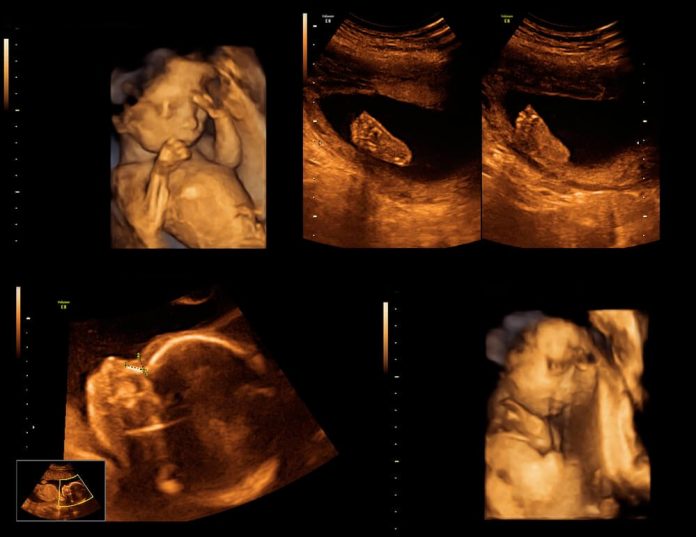

Ayrıntılı ultrasonografide anne karnındaki bebeğin her organı ayrıntılı olarak incelenir. Ayrıca bebeğin suyu, plasenta (bebeğin eşi) değerlendirilir.